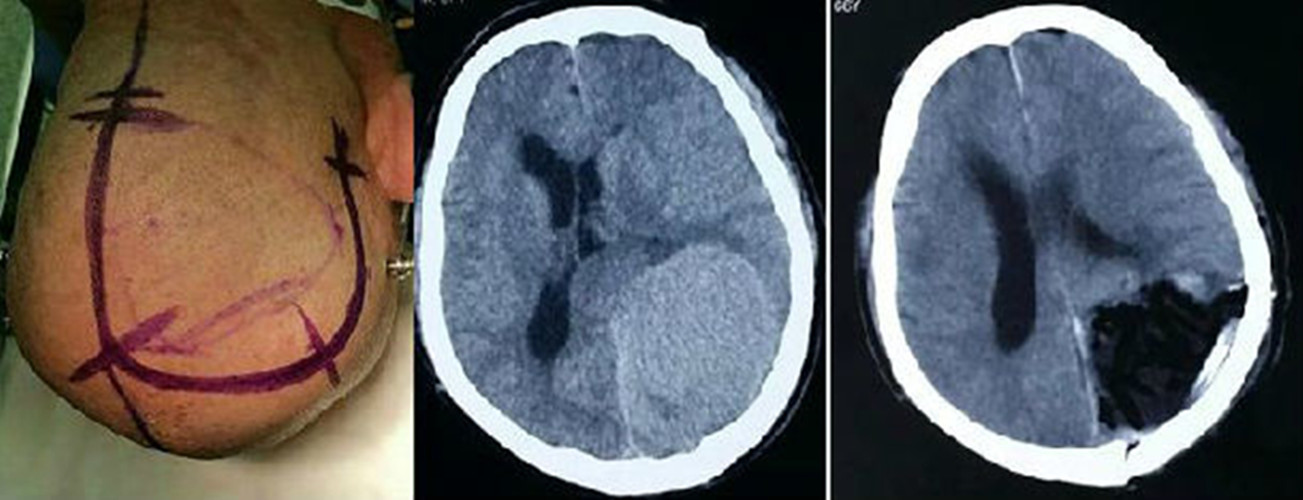

腦膜瘤圖片

腦膜瘤切除手術

腦膜瘤症狀CT